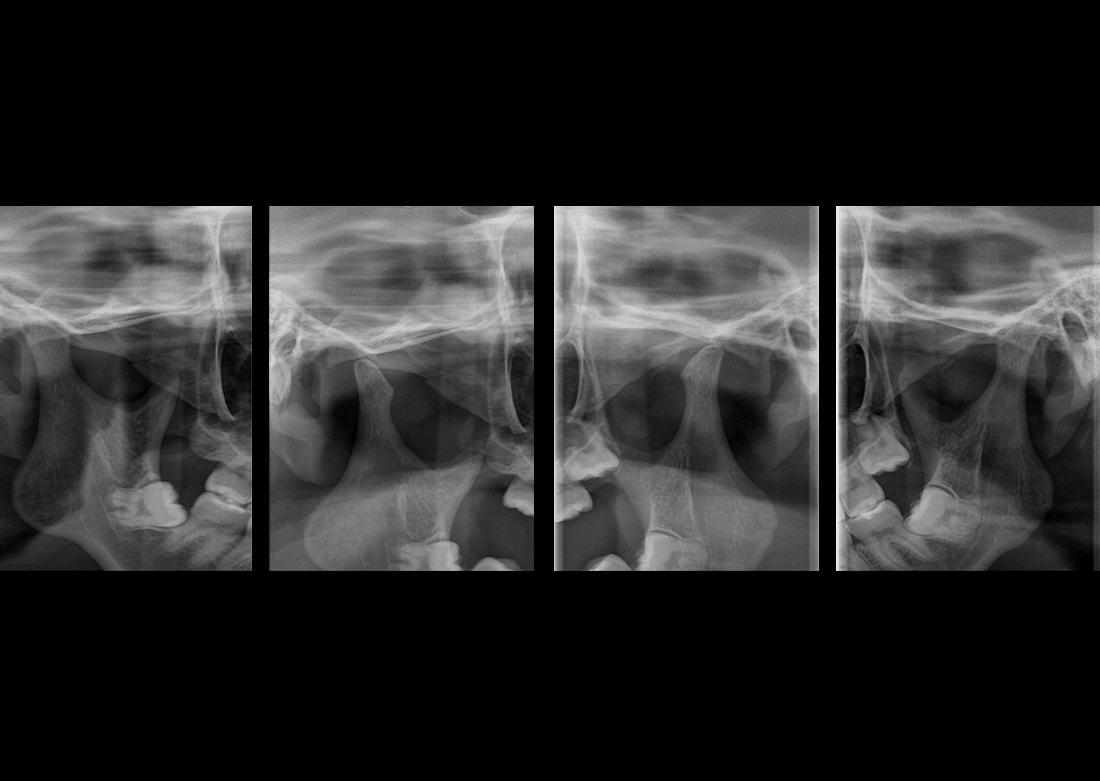

Multi Focus

Egyetlen szkennelés során öt panorámaképet készít, amelyek közül kiválasztható a legjobb minőségű felvétel.

KLİNIKAI KÉPEK

Kiváló diagnosztikai képalkotás több éves tapasztalattal és szakértelemmel.